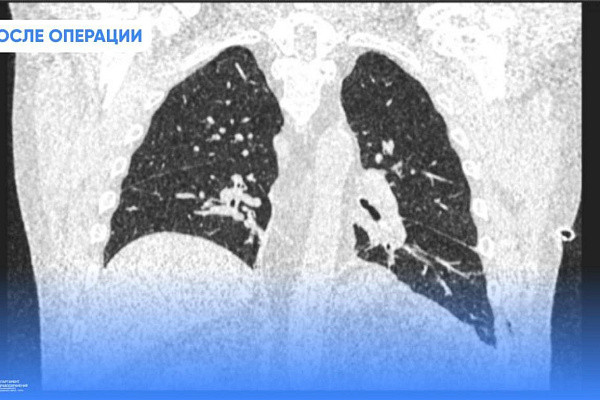

Лечение – только хирургическое. Пластика диафрагмы – это особая техника наложения шва. Операция ювелирная, поскольку толщина диафрагмы не превышает 5 миллиметров, и есть риски повредить окружающие структуры. С задачей успешно справились заведующий хирургическим отделением травмбольницы, главный торакальный хирург Югры Дмитрий Горлов и врач-хирург Евгений Николаев. Они предпочли малоинвазивную торакоскопическию методику, избежав травматического полостного доступа и дополнительной нагрузки на организм пациента.

Сразу после операции Юрий Александрович почувствовал улучшение самочувствия. Одышка больше не беспокоит, и сегодня он вновь может дышать полной грудью. Его качество жизни не пострадает. Единственное ограничение касается физических нагрузок, но и это условие необходимо соблюдать только в течение первого месяца.